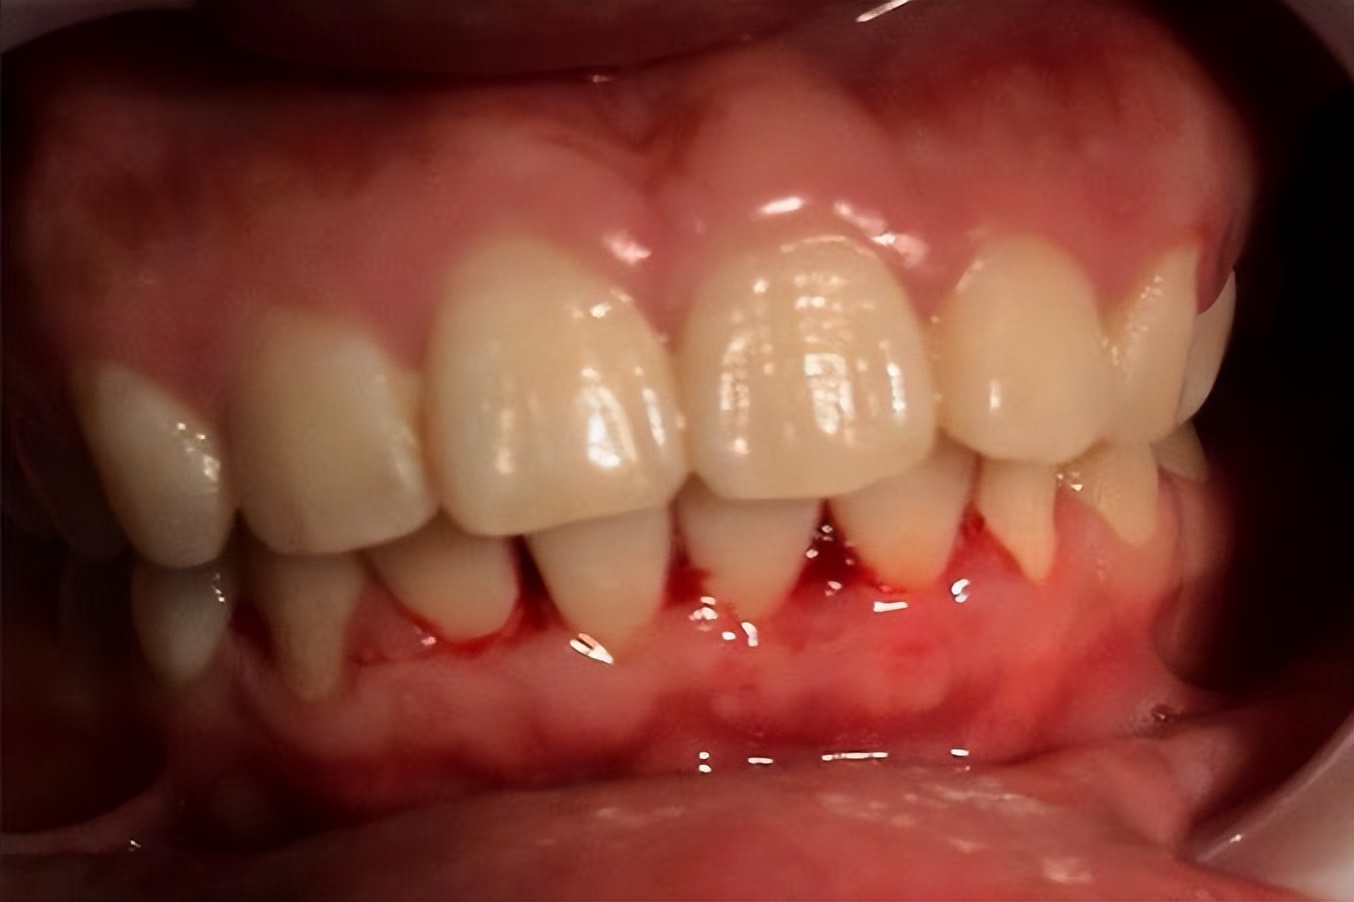

很多人刷牙时看到牙刷上有一点血,并不会太在意,甚至觉得是牙刷太硬造成的。然而如果牙龈出血频繁出现,尤其是在轻微触碰或者吃东西时就出血,这种情况往往提示牙龈组织已经存在炎症。牙龈炎和牙周炎是导致牙龈出血最常见的原因。

当口腔卫生状况不理想时,牙菌斑会逐渐堆积在牙齿和牙龈边缘。菌斑中的细菌会刺激牙龈组织,导致局部炎症反应。炎症状态下,牙龈血管会变得更加脆弱,因此在刷牙或咀嚼食物时就容易出血。然而问题并不仅仅局限在口腔。

牙龈长期炎症可能让细菌和炎症因子进入血液循环,从而影响全身系统。一些研究已经发现,牙周炎患者发生心血管疾病的风险明显增加。例如某些大型流行病学研究显示,牙周炎患者出现冠心病的概率比牙龈健康人群高出约20%到30%。此外,牙龈出血还可能与血糖状态有关。